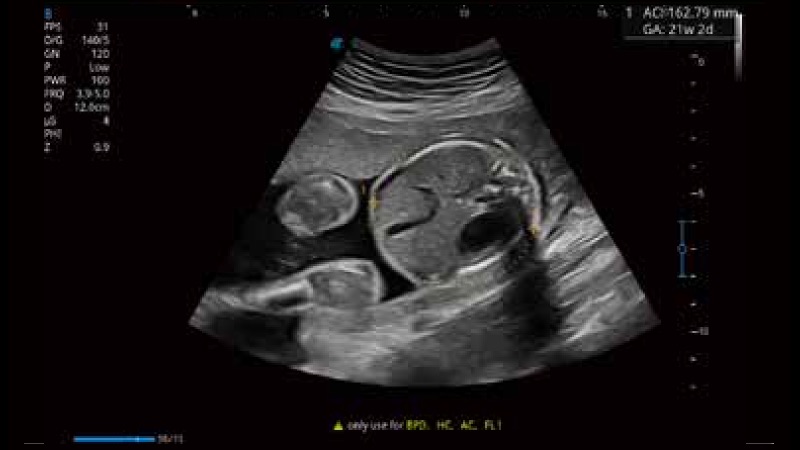

開立醫(yī)療通過不斷的技術(shù)創(chuàng)新,為大眾的生命健康提供持續(xù)關(guān)愛。P12 Plus采用全新一代超聲成像平臺(tái),新平臺(tái)旨在將真實(shí)還原組織解剖結(jié)構(gòu)作為首要目標(biāo)。平臺(tái)采用全新集成化硬件模塊,搭載新一代芯片,系統(tǒng)性能得到大幅提升,為您的診斷提供了豐富的臨床信息。優(yōu)異的圖像表現(xiàn),豐富的探頭配置,全面的應(yīng)用功能,為您日常診斷提供了可靠的助手。

彩色多普勒超聲診斷系統(tǒng)